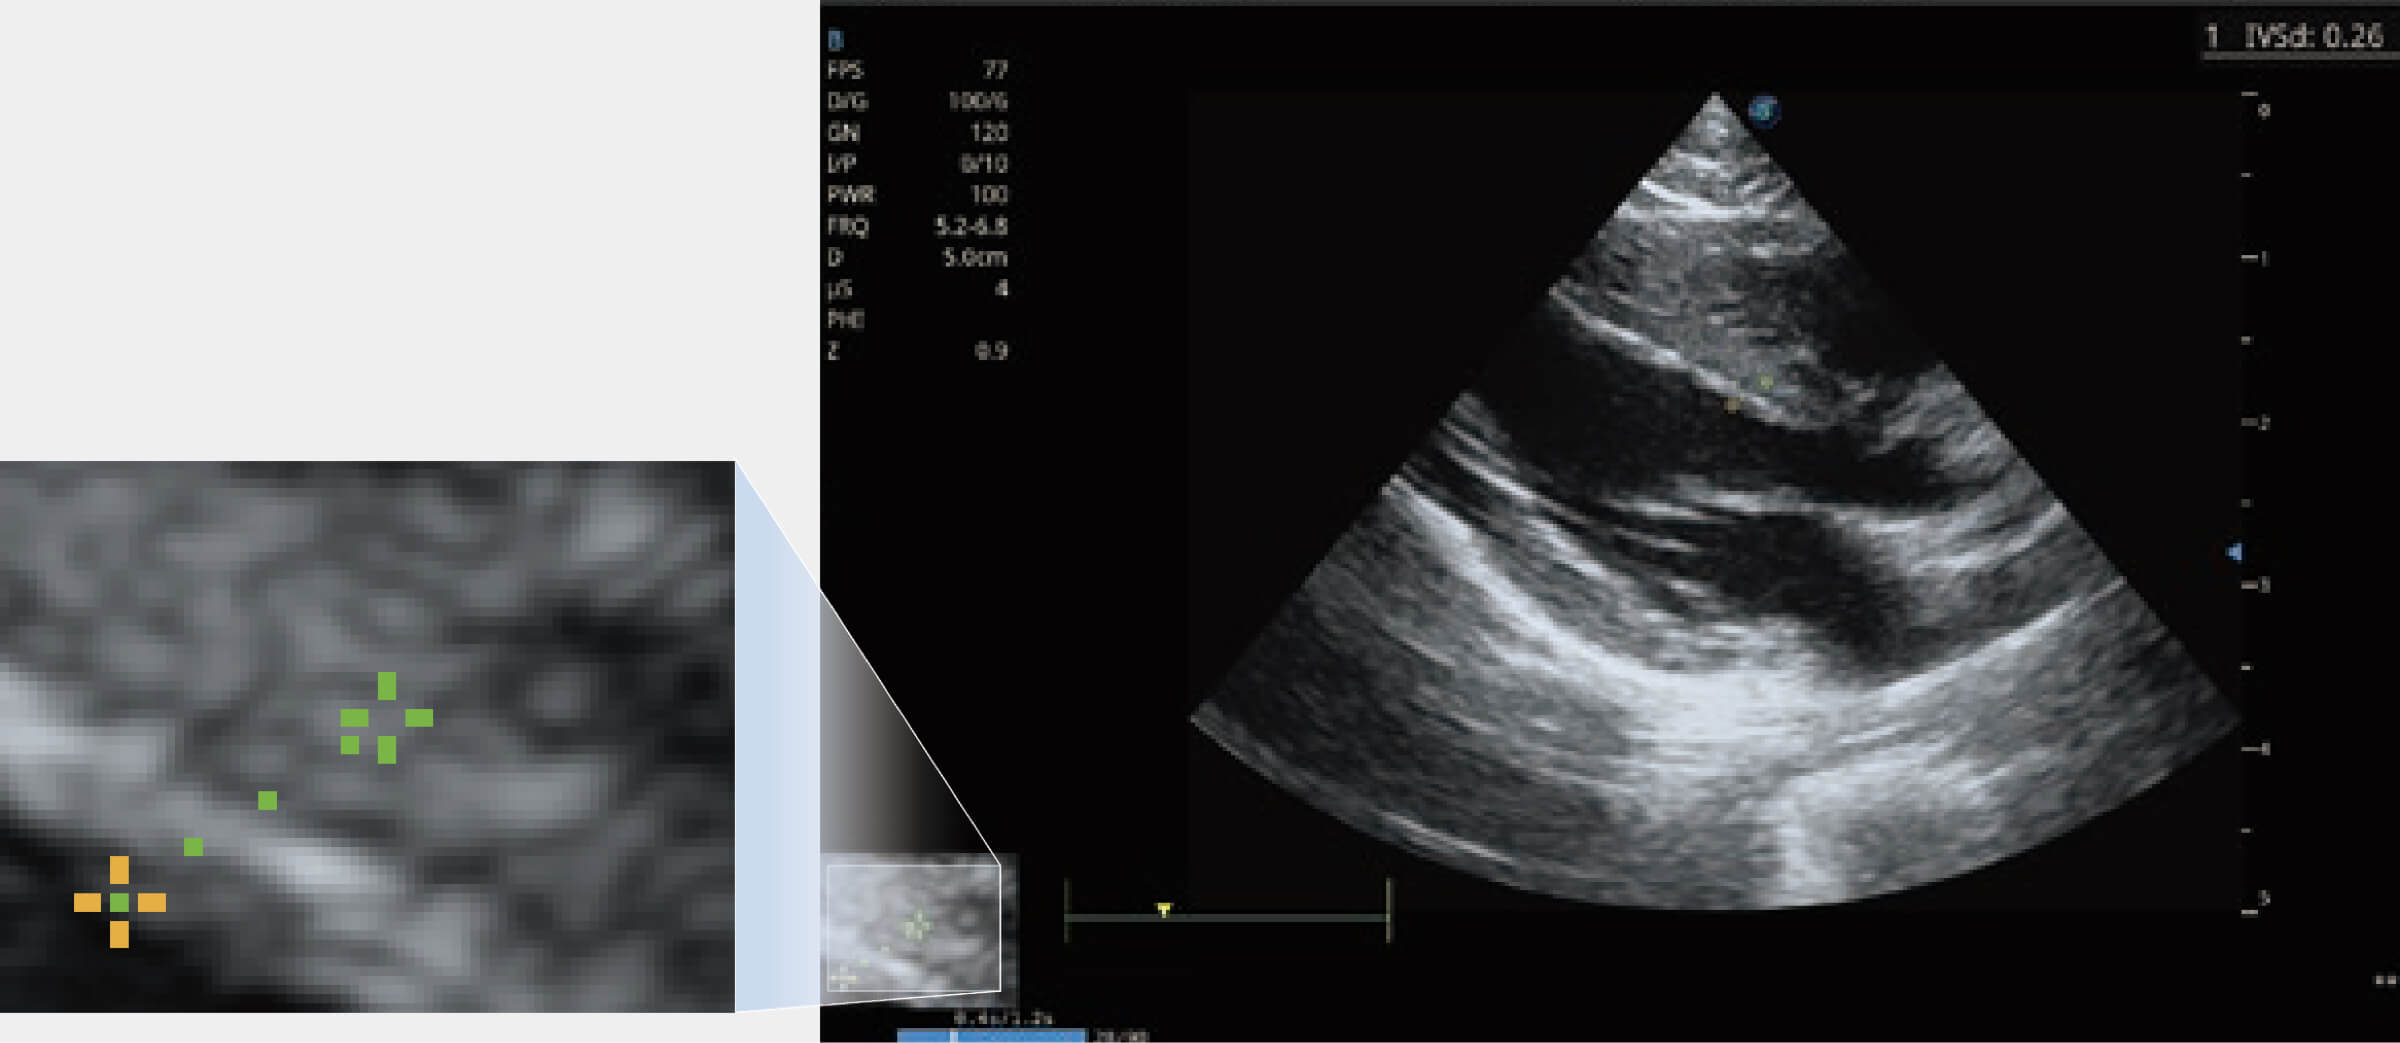

通過心肌識別技術(shù)與二維斑點(diǎn)追蹤技術(shù)相結(jié)合,對心臟的超聲圖像進(jìn)行量化分析。計算心肌17個節(jié)段的應(yīng)變、應(yīng)變率、速度、位移等,并通過牛眼圖的形式進(jìn)行呈現(xiàn)。

通過360度任意調(diào)節(jié)3條M型取樣線,在同一心動周期上觀察心臟不同位置的運(yùn)動曲線,得到準(zhǔn)確的心功能測量數(shù)據(jù),有效評估心肌運(yùn)動及左心室功能。